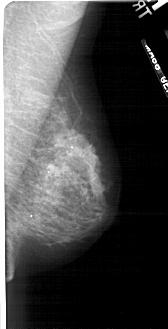

A_1723_1.RIGHT_MLO

RIGHT_MLO LINES 4921 PIXELS_PER_LINE 2506 BITS_PER_PIXEL 12 RESOLUTION 43.5 NON_OVERLAY